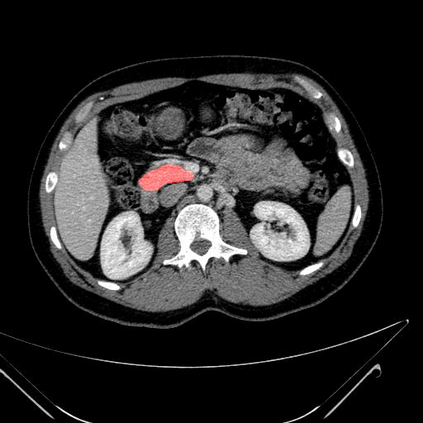

In this paper, we adopt 3D Convolutional Neural Networks to segment volumetric medical images. Although deep neural networks have been proven to be very effective on many 2D vision tasks, it is still challenging to apply them to 3D tasks due to the limited amount of annotated 3D data and limited computational resources. We propose a novel 3D-based coarse-to-fine framework to effectively and efficiently tackle these challenges. The proposed 3D-based framework outperforms the 2D counterpart to a large margin since it can leverage the rich spatial infor- mation along all three axes. We conduct experiments on two datasets which include healthy and pathological pancreases respectively, and achieve the current state-of-the-art in terms of Dice-S{\o}rensen Coefficient (DSC). On the NIH pancreas segmentation dataset, we outperform the previous best by an average of over 2%, and the worst case is improved by 7% to reach almost 70%, which indicates the reliability of our framework in clinical applications.